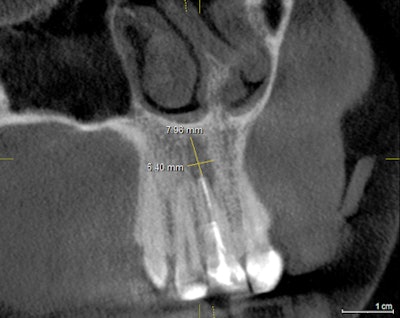

I recently scanned a patient who presented for a consultation to improve his smile and replace a number of missing teeth. The 25-year-old male in good health underwent all the conventional diagnostics, including clinical, periodontal, photographic, and periapical radiographic examination.

A number of findings made it clear that the patient required an enhanced CBCT evaluation to complete a dental examination. As usual, the 3D images were helpful in many ways to present the case, and they gave the patient the necessary information to move forward with a full-mouth rehabilitation.

Please review and consider how the CBCT images aided both diagnosis and case acceptance for these two patients.